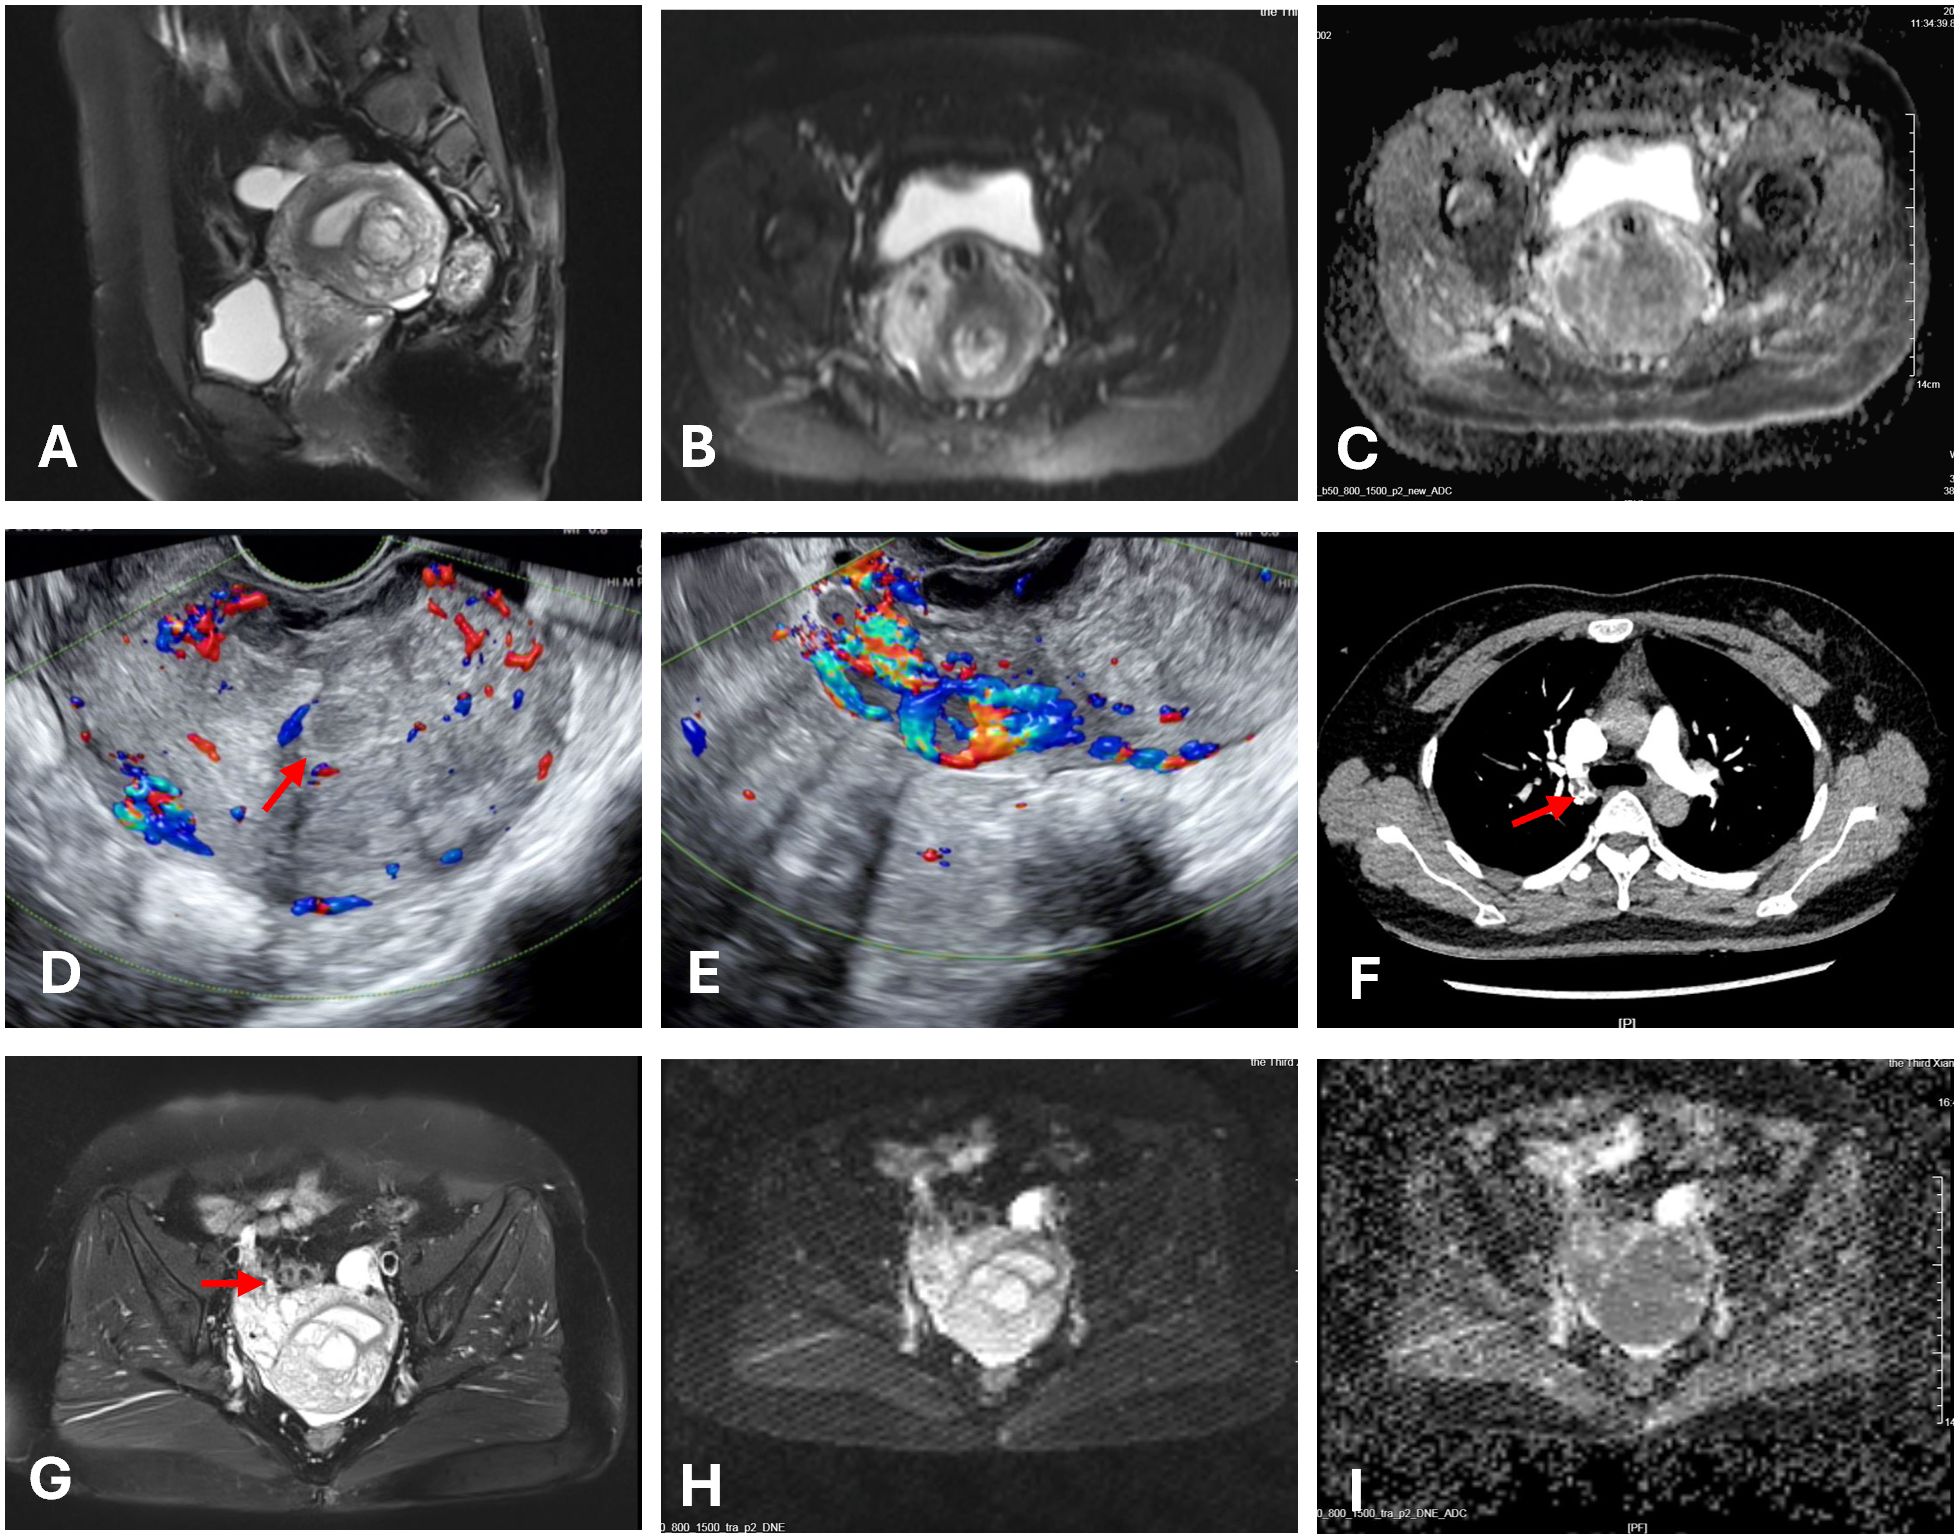

Figure 1. Images of the mass. The red arrow indicates the mass. (A) Multiple nodular lesions in the posterior uterine wall. (B, C, H, I) The tumor showed high signal on DWI and low signal on the ADC. (D) Ultrasonography shows multiple ill-defined hypoechoic nodules coalescing in the myometrium. (E) Diffuse linear hypoechoic nodules along arcuate vessels (anterior uterine wall) and right parametrial vessels, with increased blood flow signals. (F) CTA showed filling defects within the right pulmonary artery. (G) Nodular and tortuous tubular structures which shares similar MRI signals with the uterine mass were suggestive of angioleiomyoma.

In August 2023, a 42-year-old female patient was admitted to our hospital due to prolonged menstrual periods. Transvaginal ultrasound revealed a 30 × 30 mm hypoechoic nodule at the right wall of the uterine fundus, protruding approximately 20% into the uterine cavity, suggestive of fibroid. Magnetic resonance imaging (MRI) demonstrated multiple nodular lesions in the posterior uterine wall, the largest one measuring 28 × 26.2 × 26.4 mm and protruding into the uterine cavity (Figures 1A–C). These findings were consistent with multiple fibroids, including partially submucosal fibroids. Hysteroscopic examination revealed tongue-like polyps in the posterior uterine wall. The polyp was resected, however, the polypoid lesion exhibited poorly defined borders with the myometrium, indicating deeper myometrial involvement during resection (Figures 2A, B). Postoperative histological examination revealed nodular hyperplasia of stromal cells with focal proliferative endometrium within the mass. Endometrial stromal nodules or other neoplastic lesions could not be excluded. Postoperatively, the patient’s menstrual periods normalized, and did not adhere to the recommended further therapy and regular follow-up.

The patient was readmitted in September 2024 for an irregular follow-up. Ultrasonography revealed multiple hypoechoic nodules with ill-defined margins and a coalescent appearance within the uterine parenchyma. Diffusely distributed linear hypoechoic nodules were noted along the arcuate vessels of the anterior uterine wall and right parametrial vessels, with relatively abundant blood flow signals (Figures 1D, E). MRI revealed an increase in lesion size compared to previous imaging studies, with current dimensions of 58 × 46 × 52 mm. Nodular and tortuous tubular structures were observed in the right anterior uterine region and surrounding tissues, with mild T1 and prolonged T2 signals and marked enhancement on contrast imaging, which shares similar MRI signals with the uterine mass (Figures 1G–I). These imaging findings were suggestive of angioleiomyoma. The patient denied abdominal pain, distension, edema, or urinary symptoms. The patient had no significant prior medical history and reported no family history of malignancy. On physical examination, the uterus was enlarged to the size of a 2-month gestation, with firm consistency and no tenderness. No abnormalities were observed in bilateral adnexal regions. Laboratory findings showed a D-dimer level of 0.87 mg/L, fibrinogen level of 4.22 g/L, lactate dehydrogenase (LDH) of 166 U/L, and cancer antigen (CA)-125 of 9.88 U/mL. Routine blood and urine tests, electrocardiography (ECG), and echocardiography were all within normal limits.

Computed tomography (CT) pulmonary angiography (CTA), combined with abdominal CT, revealed multiple pulmonary emboli in the right pulmonary artery (Figure 1F), accompanied by filling defects in the right ovarian vein. Doppler ultrasonography of the bilateral iliac veins, lower extremity veins, and inferior vena cava revealed normal findings. Due to the patient’s fertility preservation request and the presence of an intracavitary protruding mass, hysteroscopic resection was initially performed. Intraoperative findings revealed multiple polypoid projections in the uterine cavity, with the largest lesion (approximately 1.5 cm in diameter) located on the posterior wall. A myoma-like protrusion with approximately 20% intracavitary extension was also identified on the posterior wall. Postoperative histological examination revealed nodular hyperplasia of the endometrial stroma with focal infiltration into the myometrium, while significant cytological atypia was absent. Immunohistochemistry showed positive expression of CD10, estrogen receptor (ER, 90%), and progesterone receptor (PR, 95%), weakly positive Cyclin D1 in approximately 20% of tumor cells, negative staining for desmin, smooth muscle actin (SMA), h-caldesmon, and cytokeratin. Ki67 index (15% in hotspot areas). These findings raised strong suspicion for LGESS. A multidisciplinary team (MDT) discussion was convened following the second hysteroscopic procedure. The uterine mass was considered highly suggestive of LGESS. Regarding the pulmonary embolism, which presented on CTA as multiple, irregular, filling defects with heterogeneous enhancement on post-contrast, these features are more consistent with tumor thrombus rather than bland thrombus. However, considering the absence of respiratory symptoms and the limited extent of involvement, surgical embolectomy was not pursued.

The diagnosis of LG-ESS is challenging due to its nonspecific clinical presentation and inconclusive imaging findings in the early stages. Ultrasonography and MRI often fail to differentiate LG-ESS from benign conditions such as leiomyoma, and the reported preoperative biopsy misdiagnosis rate is as high as 40% (4). In this case, the MRI revealed multiple nodules in the posterior uterine wall that were isointense on T1WI, slightly hyperintense on T2WI, showing high signal on DWI and low signal on ADC. These findings are helpful in differentiating the lesions from leiomyoma. A tentative pathological diagnosis was made during the first hysteroscopic procedure, based on the observation of deep myometrial invasion. This emphasizes the importance of obtaining sufficient tissue during sampling for accurate diagnosis. Although vascular invasion is a recognized feature of LG-ESS, involvement of major vessels such as the pulmonary artery, as observed in this case, is exceedingly rare. In this case, the tumor cells of LGESS appear round to oval, resembling those of proliferative-phase endometrial stromal cells and are characterized by infiltrative growth into the myometrium, this contrasts with the fascicular structure of bland, spindle-shaped smooth muscle cells characteristic of IVL. Moreover, the IHC strong positivity for CD10, ER, and PR, and negativity for h-caldesmon, which represents a key characteristic of LGESS. The focal and weak positivity for SMA and desmin may indicate smooth muscle differentiation in the tumor.